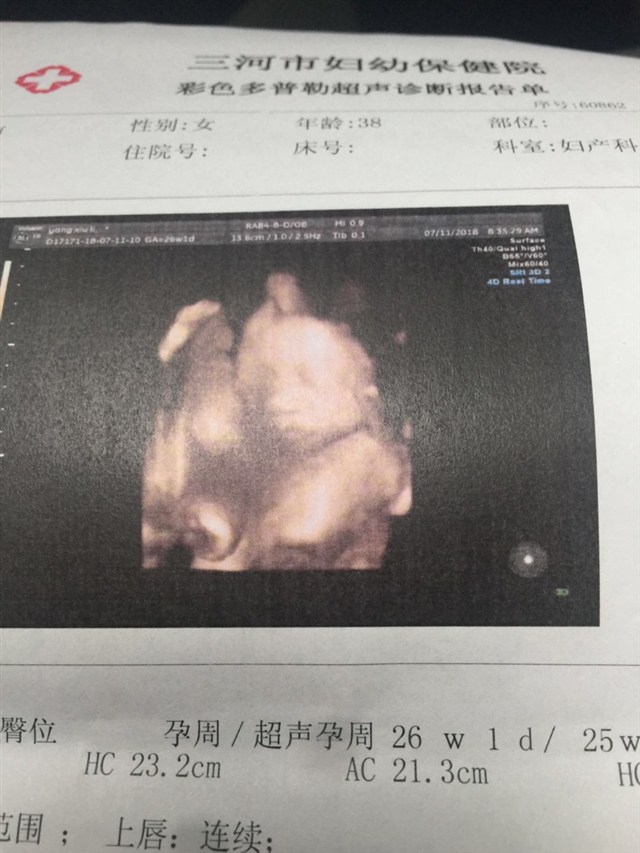

对啊,这是第三胎了。已经查了四维但不知道男女。没敢问